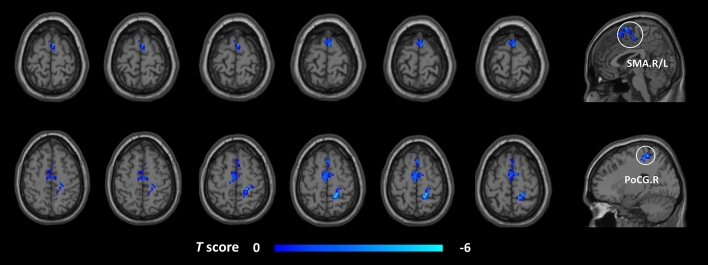

In the FC analysis, we used the right cerebellar lobule VIII, right FFG, right ITG, and left PCL as ROIs to analyze the changes in the whole-brain FC in these brain regions in the post-taVNS patients. Compared to the pre-taVNS patients, the post-taVNS patients had enhanced FC in the right ITG with the bilateral orbitofrontal gyrus (OFG), bilateral angular gyrus (ANG), left inferior parietal lobule (IPL), and bilateral posterior cingulate gyrus (PCG) (Table 3; Fig. 2). Meanwhile, compared to the pre-taVNS patients, the post-taVNS patients had reduced FC of the right cerebellar lobule VIII with the bilateral supplementary motor area (SMA) and right PoCG (Table 4; Fig. 3). The correlation analysis revealed that the changed FC of ITG-IPL was significantly and positively correlated with the changes in headache intensity.

Brain areas indicating changed FC with the cerebellar lobule VIII in the post-taVNS patients compared to the pre-taVNS patients (GRF corrected, voxel p < 0.005, cluster p < 0.05). FC functional connectivity, taVNS transcutaneous auricular vagus nerve stimulation, post-taVNS after taVNS treatment, pre-taVNS before taVNS treatment, GRF Gaussian random field, AAL automated anatomical labeling, MNI Montreal Neurological Institute, SMA supplementary motor area, PoCG postcentral gyrus, L left, R right.

| 200 | SMA.R/L | 3 | 3 | 69 | − 4.10 |

| 33 | PoCG.R | 18 | − 39 | 60 | − 5.10 |

Figure 3.

Brain regions indicating reduced seed-based FC between the post- and pre-taVNS patients (GRF corrected, voxel p < 0.005, cluster p < 0.05). The cool color bar represents areas where the FC of the post-taVNS patients is smaller than the pre-taVNS patients. FC functional connectivity, taVNS transcutaneous auricular vagus nerve stimulation, post-taVNS after taVNS treatment, pre-taVNS before taVNS treatment, MwoA migraine without aura, GRF Gaussian random field, SMA supplementary motor area, PoCG postcentral gyrus, R right, L left.

Altered FC of the posterior cerebellar lobes in MwoA patients after taVNS treatments

Our study indicated that the cerebellum of patients after taVNS has fewer functional connectivity to SMA and PoCG. The cerebellum, SMA, and PoCG are part of the vestibular cortical network (VCN)115. The vestibular cortical network involves motor balance and spatial navigation116. Abnormal activation of the VCN is found in migraine patients compared to HCs105. Follow-up of migraineurs shows that they often feel persistent vertigo, affecting their quality of life117. Vertigo symptoms in migraine patients may persist throughout the illness118,119. Regarding neural projections, the SMA receives fibre projections from the cerebellum120. Several pain-related studies have identified abnormal alterations in the SMA121,122. PoCG is involved in identifying pain information123. Meanwhile, the PoCG is the primary somatosensory cortex that regulates the corresponding behaviors based on sensory information124. Moreover, the FC of the PoCG was altered in resting-state fMRI investigations of migraine8,27,125. Thus, taVNS might participate in modulating the intrinsic connectivity within the VCN of MwoA patients, which is a brain network associated with homeostasis. Meanwhile, taVNS may modulate the brain functional connectivity patterns associated with the pain of MwoA patients.